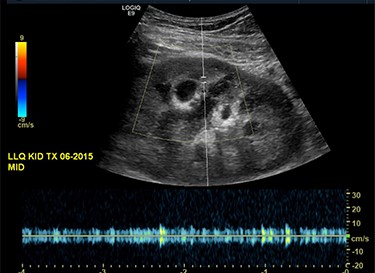

Our patient is a 35-year-old female with a history of Type 1 diabetes and hypertension who underwent SPK transplantation in 2015. The pancreas transplant was performed with systemic venous drainage and enteric exocrine drainage. Kidney transplantation was performed intraperitoneally in the left lower quadrant, with standard anastomoses performed between left external iliac vessels and renal artery/vein [1]. She presented to the emergency room 5 years after her transplantation with 24 h of severe Lt lower abdominal pain, nausea and vomiting with tachycardia and leukocytosis up to 22.6. The patient was diagnosed with sepsis secondary to UTI. Upon evaluation, she was anuric, and her creatinine was 5.45 mg/dl from 2.15. Computed tomography (CT) abdomen pelvis without contrast showed hydronephrosis of the donor kidney (Fig. 1). Doppler ultrasound was performed and showed no flow to the donor kidney (Fig. 2). She was urgently taken to the operating room for exploration. Intraoperatively, we found that the renal artery and vein of the transplanted kidney was strangulated by the left fallopian tube and respective ovary (Fig. 3). The transplanted kidney was noted to be gangrenous and ischemic (Fig. 4). In addition, intraoperative Doppler confirmed no arterial blood flow, and the decision was made to perform a transplant nephrectomy. The remainder of her hospital course was unremarkable. The patient was subsequently re-listed for a kidney transplant.

Ultrasound of the transplanted kidney showing no blood flow within the main renal artery or vein.